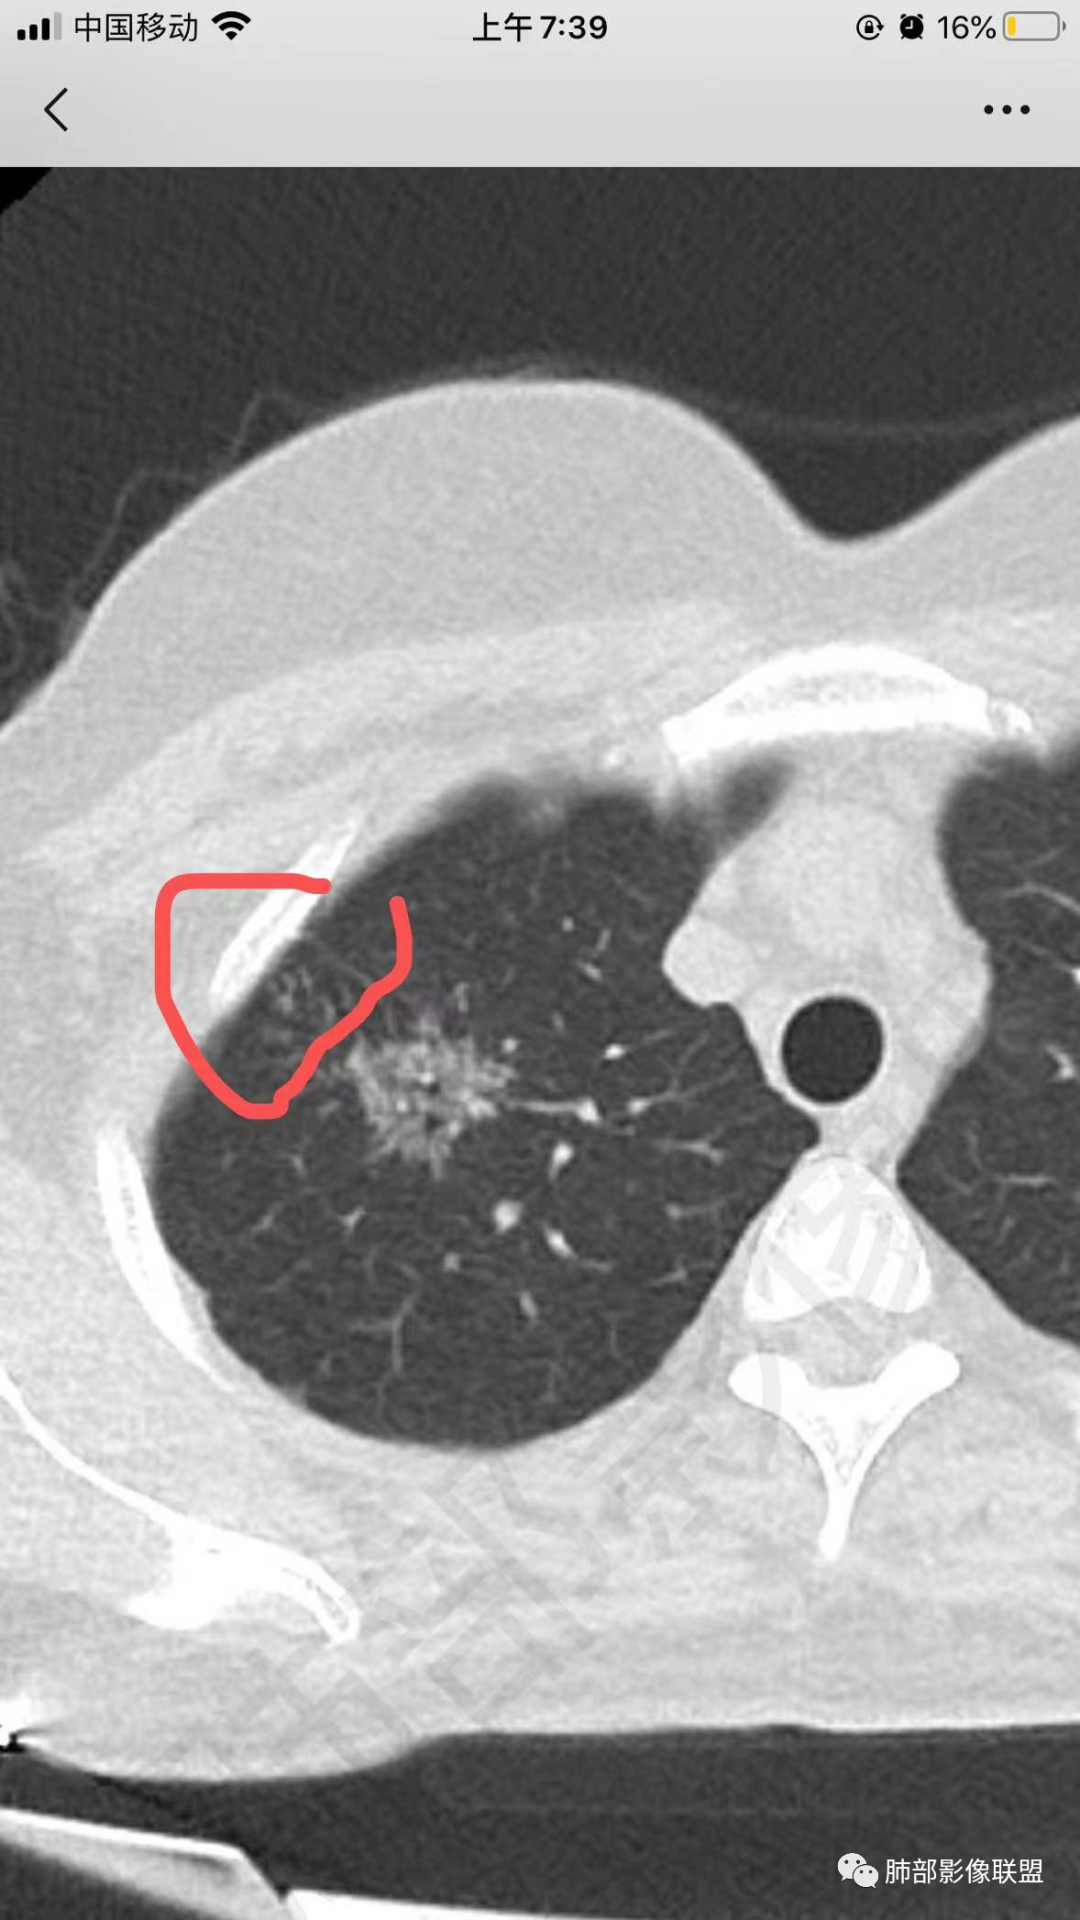

病例特点:52岁女性,体检患者。

影像特点:右肺上叶混合磨玻璃影,边界清晰,结构松散,内有多结节堆积及支气管扩张影,可见小叶间隔增厚,并局部增厚的小叶间隔上亦存在微结节,胸膜侧可见纤细索条,病灶周围可见多发微结节影。

总体分析:从病灶分布来看符合结核的好发位置,影像表现也符合结核的多态性,且出现卫星灶。由于有边界清晰的GGO,需要鉴别腺癌,虽然此病例有边界清晰的GGO,但是它的GGO的边缘有结节感,呈多结节堆积,而腺癌的GGO缺乏这种“多结节堆积感”,另外,此病例也没有发现腺癌的胸膜凹陷征、毛刺征及月牙铲等。

右上叶磨玻璃影,有结节感,首先考虑结核,类似于烟花征